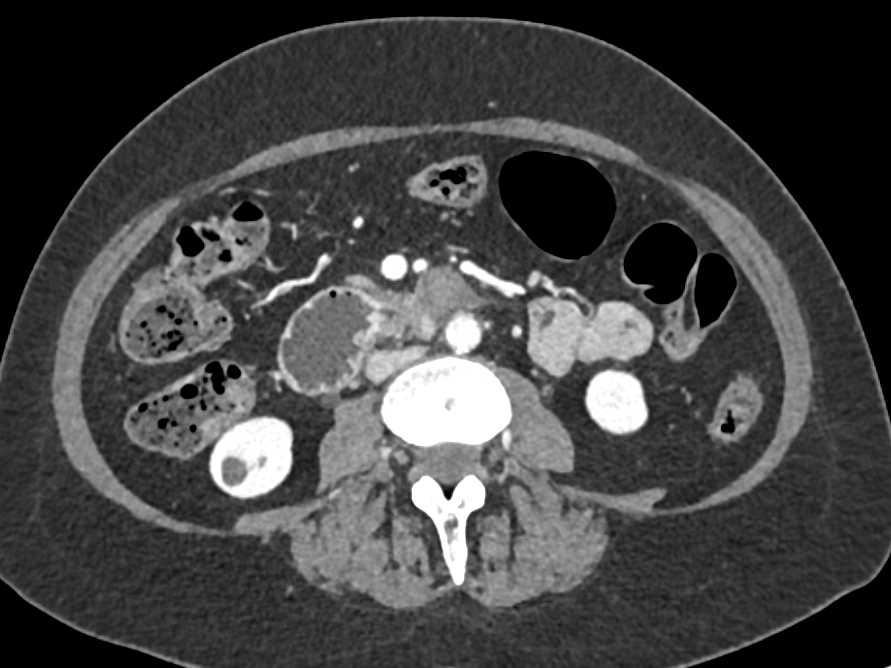

Duodenal Carcinoma with Obstruction